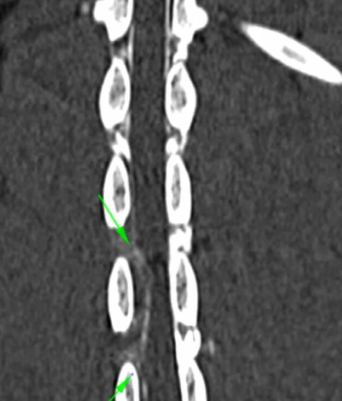

La hernia discal en perros ocurre cuando el núcleo pulposo de un disco intervertebral se desplaza y presiona contra la médula espinal o los nervios. Este desplazamiento puede causar inflamación, dolor y problemas de movilidad en el perro.

Hay dos tipos de hernias de disco en perros: la hernia de disco cervical, que afecta a la columna cervical, y la hernia de disco lumbar, que afecta a la columna lumbar.

Cirugía avanzada: En casos graves, puede ser necesario